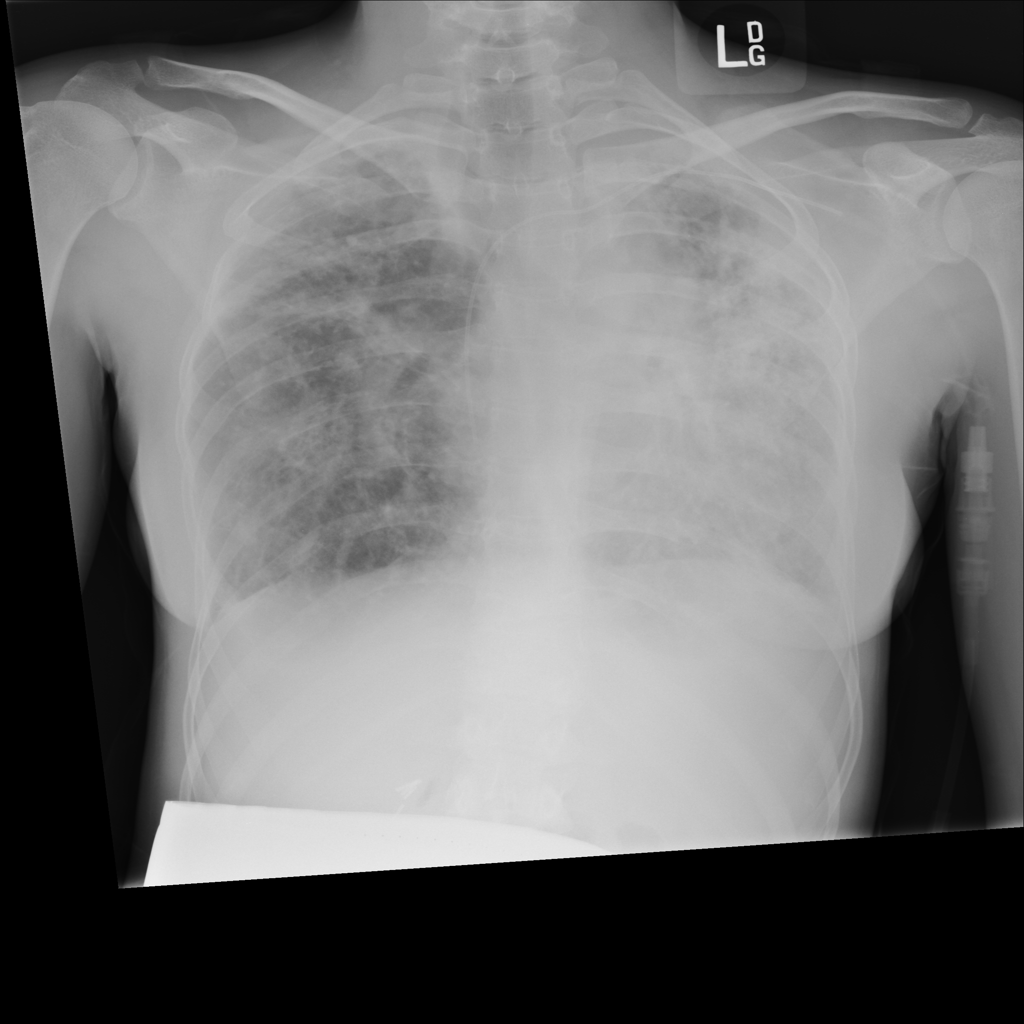

PAT-A380 · IMG-002Consolidation

PAT-A380 · IMG-002

AP